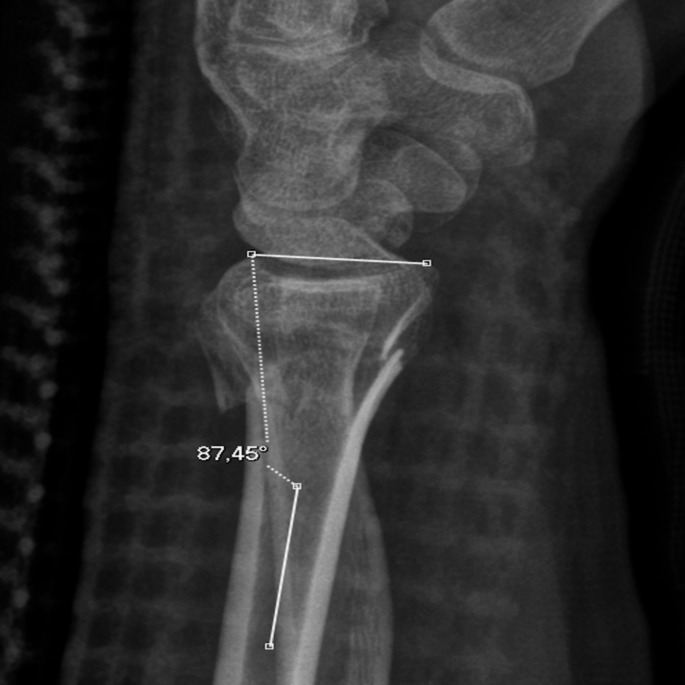

桡骨远端骨折是最常见的骨折类型之一。侧位x线片评估的桡骨远端关节面背侧倾斜常用于确定正确的治疗方法。本报告旨在强调在获得桡骨远端x线片时正确前臂定位的重要性,以及旋前和旋后对桡骨背侧倾斜测量的影响。它提出了一个病例35岁的男性与运动相关的跌倒期间持续的左侧桡骨远端骨折错位。

Distal radius fractures are one of the most prevalent fracture types. Dorsal tilt of the articular surface of the distal radius as assessed on the lateral radiograph is often used in determining the correct treatment method. This report seeks to highlight the importance of correct forearm positioning when obtaining distal radius radiographs, and the effects of pronation and supination on dorsal tilt measurements of the radius. It presents a case of a 35-year-old male with a malaligned left-sided distal radius fracture sustained during a sports-related fall.